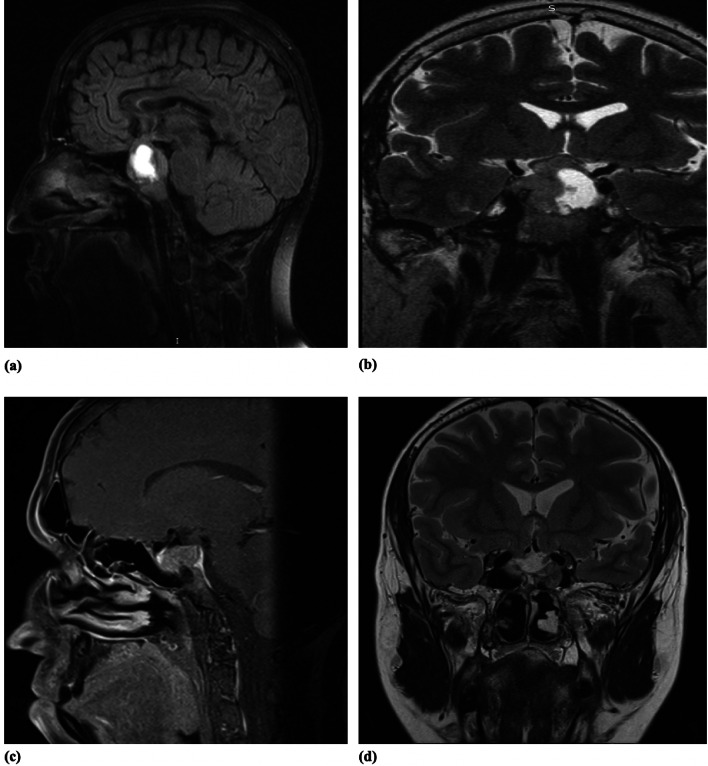

In several studies, hyperprolactinemia has been associated with increased breast cancer risk. Evidence shows that prolactin (PRL) is linked to mammary tumorigenesis, especially in postmenopausal patients, but the data remain controversial. We present a case of a 67 year-old patient with a resistant PRL-secreting PitNET who subsequently developed breast cancer. The patient was known to have persistent high PRL levels despite multimodal treatment (surgery, radiotherapy, and high doses of cabergoline). The tumor specimens obtained after transsphenoidal intervention were histologically and immunohistochemically examined for the following parameters: anterior pituitary hormones, the ki-67 labeling index, CAM 5.2 expression, ER ∝ expression, and somatostatin receptors, which revealed a densely granulated tumor with intense positivity for PRL and ER ∝ , a ki-67 labeling index of 6% and negative MGMT expression. Years later, the patient was diagnosed with breast carcinoma. Histopathological and immunohistochemical examination of the tumor specimen obtained after radical mastectomy confirmed ductal invasive breast cancer with negative immunostaining for prolactin receptors (PLRr) but positive immunostaining for estrogen (ER) and progesterone receptors (PGR) and a ki-67 labeling index of 8%. PRL is involved in mammary development and differentiation, which leads to lactation, the major driver during pregnancy, by regulating ovarian progesterone production. On the basis of the physiological actions of PRL, a role for this hormone in breast cancer has been suggested. Few cases of different types of breast carcinoma associated with hyperprolactinemia due to a pituitary tumor have been reported in the literature. The association between hyperprolactinemia and the risk of breast carcinoma is not well understood. Immunohistochemistry evaluation of PLRr can be helpful to provide information in these cases.